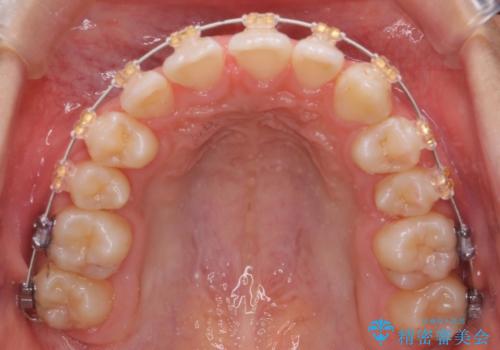

- 審美装置

- 右上の犬歯が埋伏していたため、抜歯しました。

その後、右下の小臼歯を1本抜歯し、ワイヤー矯正を行いました。

犬歯の代わりに小臼歯を配列し、最小限の抜歯の本数としました。

犬歯の両側の歯に関しては移動することにより歯槽骨が順調に回復し、上顎洞底の形態にかかわらず歯根のパラレリングを行うことができました。

犬歯の両側の歯に関しては移動することにより歯槽骨が順調に回復し、上顎洞底の形態にかかわらず歯根のパラレリングを行うことができた理由としては、年齢が10代前半と若かったからだと思います。

左上4−7については、近心傾斜をしていたため、右上3を抜かずに遠心に移動して非抜歯で治療を行う案も提案しましたが、抜歯を選択されました。結果的に深く埋まっていた右上犬歯を牽引せずにすみ、さらに歯根の向きも整えることができてよかったです。治療も比較的短期間で済みました。